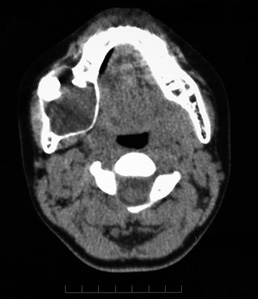

10歳 男児

X-pでは顎骨内に単房性の嚢胞様透過像を示すエナメル上皮腫の亜型。埋没歯をともなうことがあり画像のみでは含歯性嚢胞や他の嚢胞性病変との鑑別は難しい

X-pはdentigenous cystを思わせる像だが, 上皮の性状が異なる。